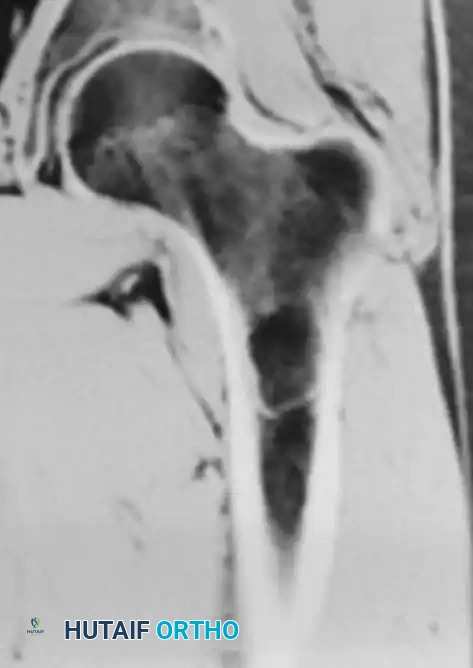

Fig. 20-19: (A) Intraosseous lipoma in the left proximal femur of a 51-year-old man. (B and C) The lesion demonstrates the same signal characteristics as normal macroscopic fat on both T1- and T2-weighted MRI sequences.

Advanced imaging is highly specific. Computed Tomography (CT) and Magnetic Resonance Imaging (MRI) reveal well-defined lesions exhibiting the exact signal characteristics of macroscopic fat (hyperintense on T1, suppressing on fat-saturated sequences). Central necrosis or targetoid calcification is frequently evident, representing infarcted adipose tissue. Because imaging is usually pathognomonic, a diagnostic biopsy is rarely necessary.

Intraosseous lipomas undergo a well-documented evolutionary process, often categorized by the Milgram classification. Early-stage lesions consist of viable adipose tissue, while later stages exhibit central necrosis, cyst formation, and dystrophic calcification due to localized ischemia.